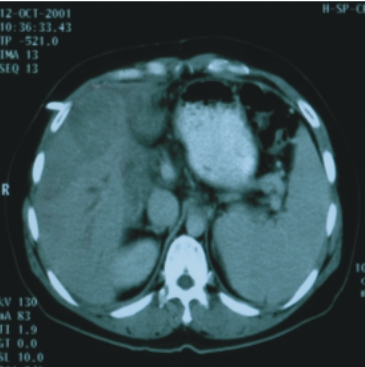

(二)肝內之肝細胞癌及膽道癌:

17例患者(其中膽道癌7例),大部分為無法手術切除或施行動脈栓塞者,其中2例膽道癌曾接受膽管支架置入術。利用此治療技術以增加腫瘤控制率及延長存活時間,同時較傳統放射治療更能保護正常肝臟之功能。平均追蹤時間為23個月。腫瘤反應率(即縮小50﹪以上的機會)85﹪,18個月之存活率75﹪,且無病患因治療而出現肝衰竭。

37歲/女性

(肝內膽道癌術後復發) |

63歲/女性(肝內膽道癌) |

||

| 90/10/12(治療前)

|

91/3/25(治療後) |

90/2/15(治療前) |

91/3/21(治療後) |

| 腫瘤大小:7x6x5公分 |

完全消失 |

腫瘤大小:6x5x5公分 |

完全消失 |